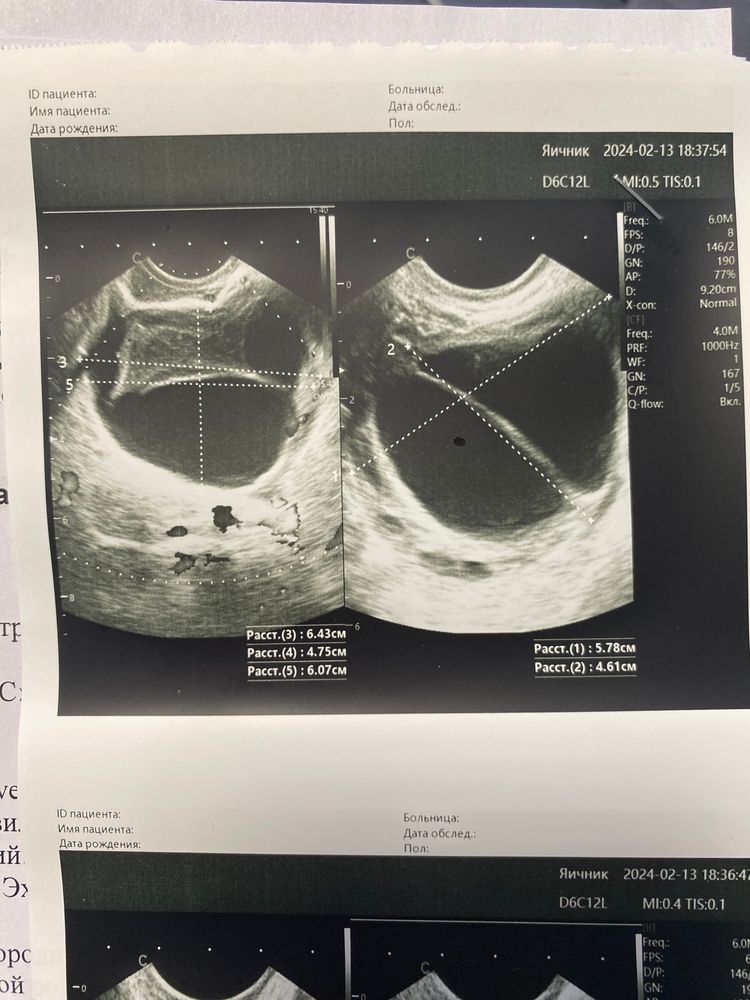

1. На дюфастоне я не ощущала овуляцию, а после самостоятельной его отмены - О была 100%! Я ее почувствовала (но скорее всего, мы с мужем опоздали на пару дней), поймала её остатки тестами и после подтвердила на узи. Мой врач сказала, что она действительно была и была такая мощная, что сейчас на месте фолликула киста желтого тела размерами 6 на 5 см. Так же на узи посмотрели эндометрий - 11 см, что тоже хороший показатель. + в мае прошлого года в каждом яичнике у меня было более 20 фолликулов, а в этот раз в правом 10-12, что тоже радует.